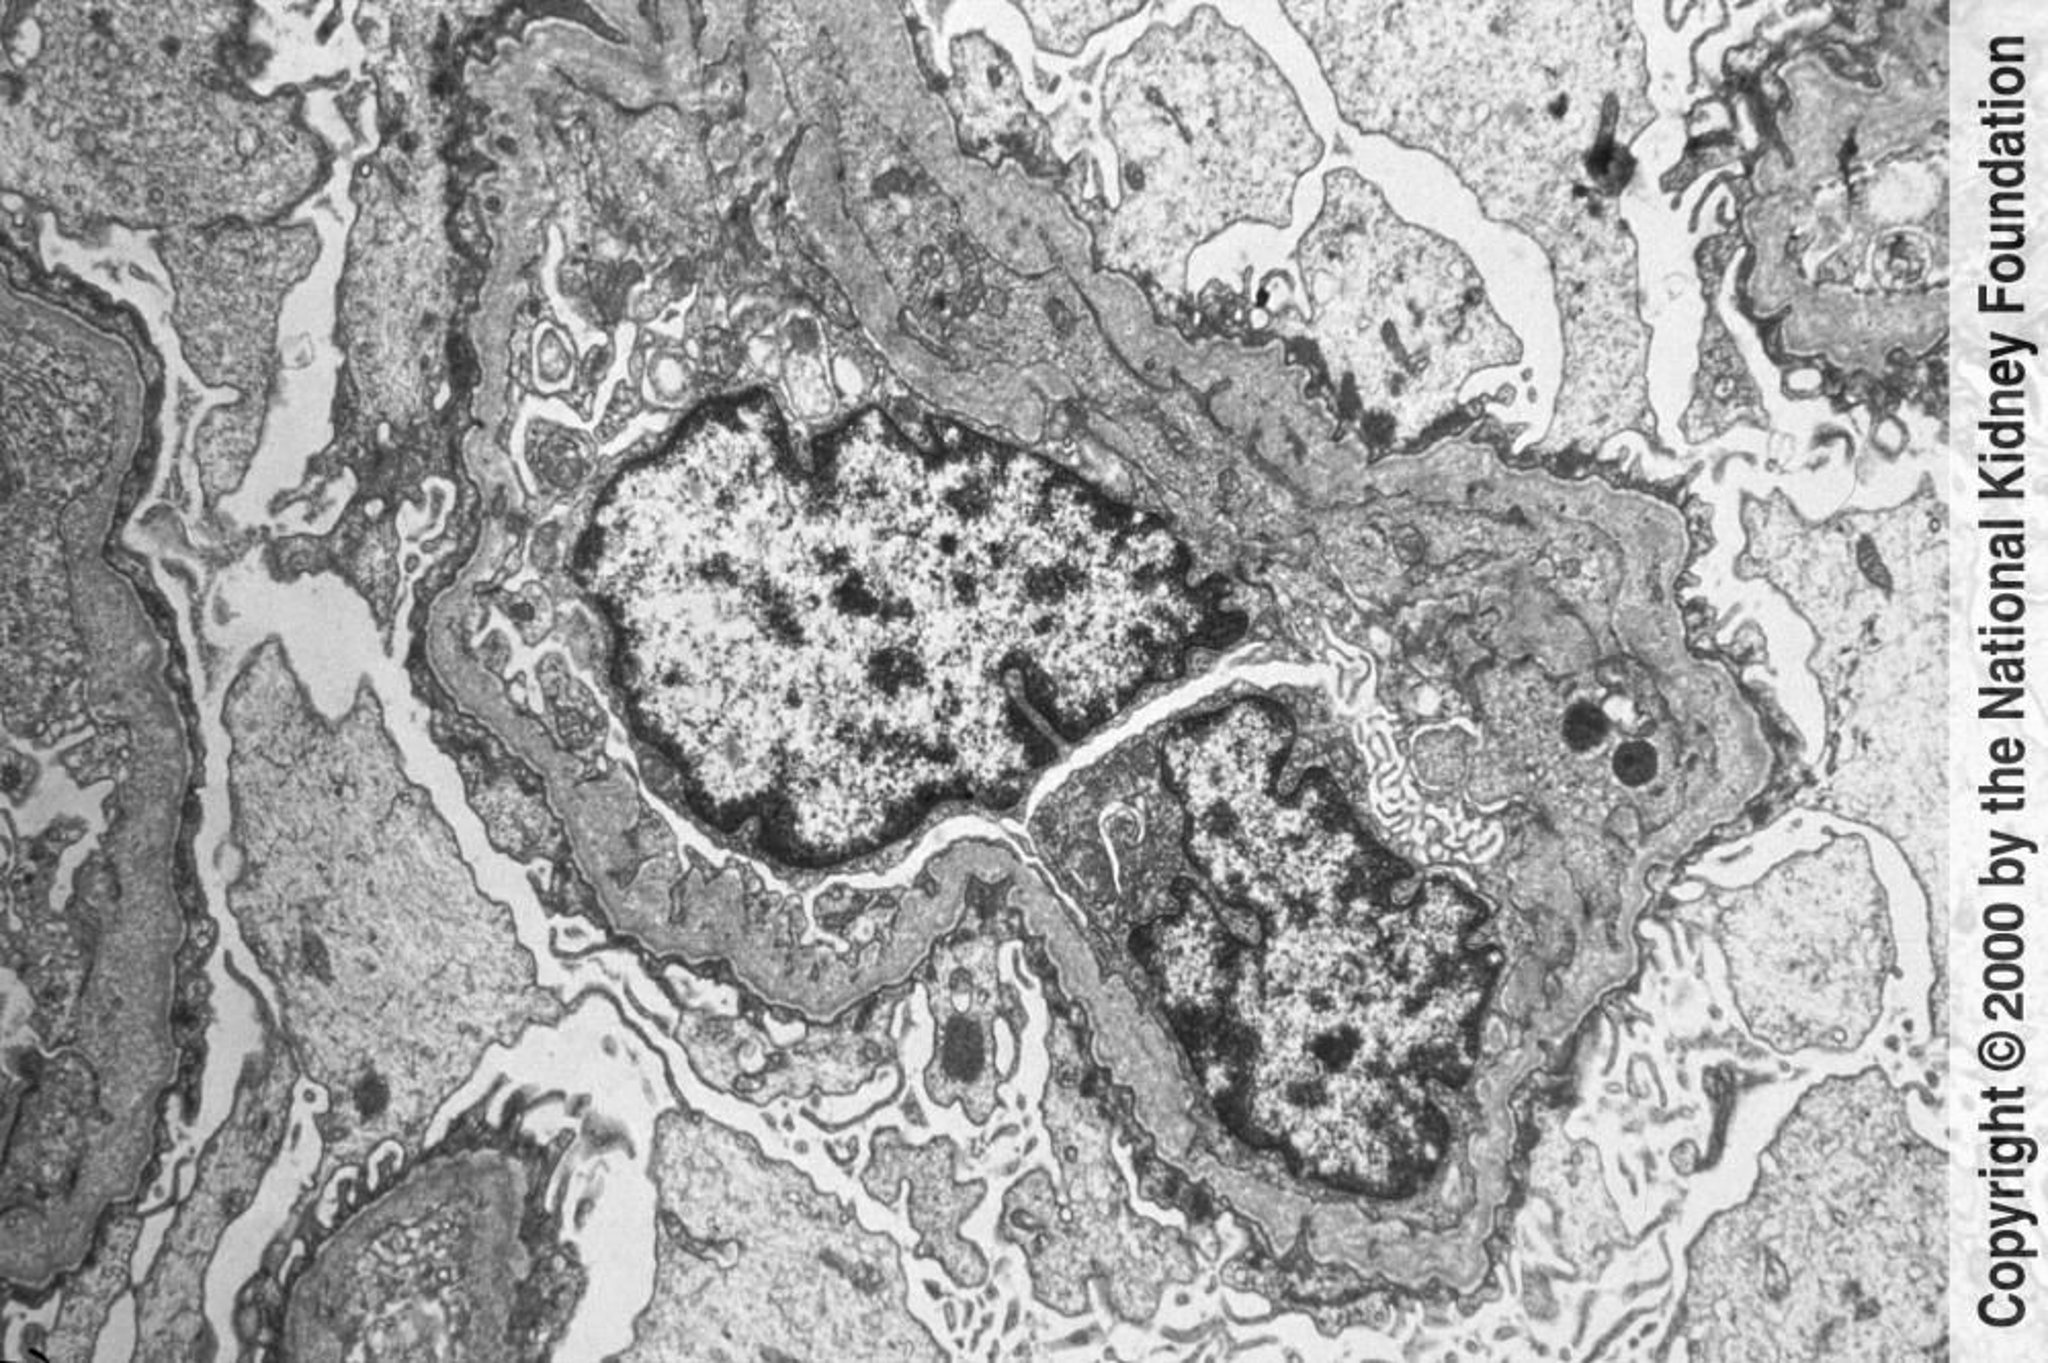

Синдром Альпорта (наследственный нефрит)

В просвечивающем электронном микроскопе видны неравномерные истончение и утолщение гломерулярной базальной мембраны с расщеплением темной пластинки (lamina densa) на волокна, образующие сеть наподобие корзины. Изменения вызваны травмой и ремоделированием (×6000).

Image provided by Agnes Fogo, MD, and the American Journal of Kidney Diseases' Atlas of Renal Pathology (see www.ajkd.org).